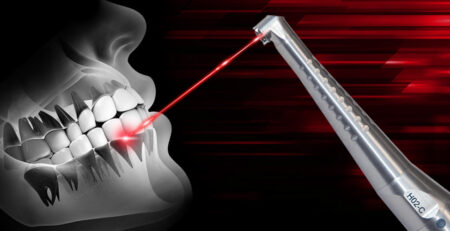

Laserul diodă LITEMEDICS: Specificații tehnice și aplicații clinice

Laserul diodă a adus o schimbare semnificativă în stomatologia modernă, oferind beneficii extinse atât pentru medici, cât și pentru pacienți.... read more

Laserul în stomatologie: Tehnologii și aplicabilitate

Cabinetele stomatologice moderne sunt în căutarea de tehnologii avansate pentru a oferi pacienților tratamente dentare de înaltă calitate. Laserul... read more